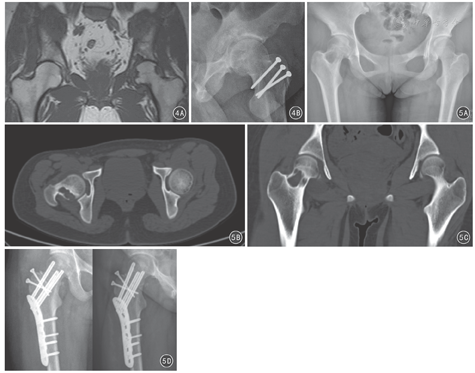

对于髋关节绒毛结节性滑膜炎、滑膜软骨瘤病、股骨头颈区骨囊肿/内生软骨瘤、髋臼底部骨囊肿/内生软骨瘤等良性病变,传统方法是经SP入路(Smith-Peterson approach)或后外侧入路切开关节,进行清理和处理。近年来也有采用关节镜技术处理[17,18,19]、经股骨颈开窗技术处理[20]、经髂骨/耻骨开窗处理[21]等,方法不一,但均存在处理不准确、不彻底的问题,同时存在股骨头坏死、易复发、髋周软组织创伤等风险。SHD给这类病变的处理带来了极大的变革,可以在不损伤股骨头血液循环的前提下进行病灶的彻底清理、开窗、刮除、植骨、准确摘取病变组织等操作。见图4、图5。